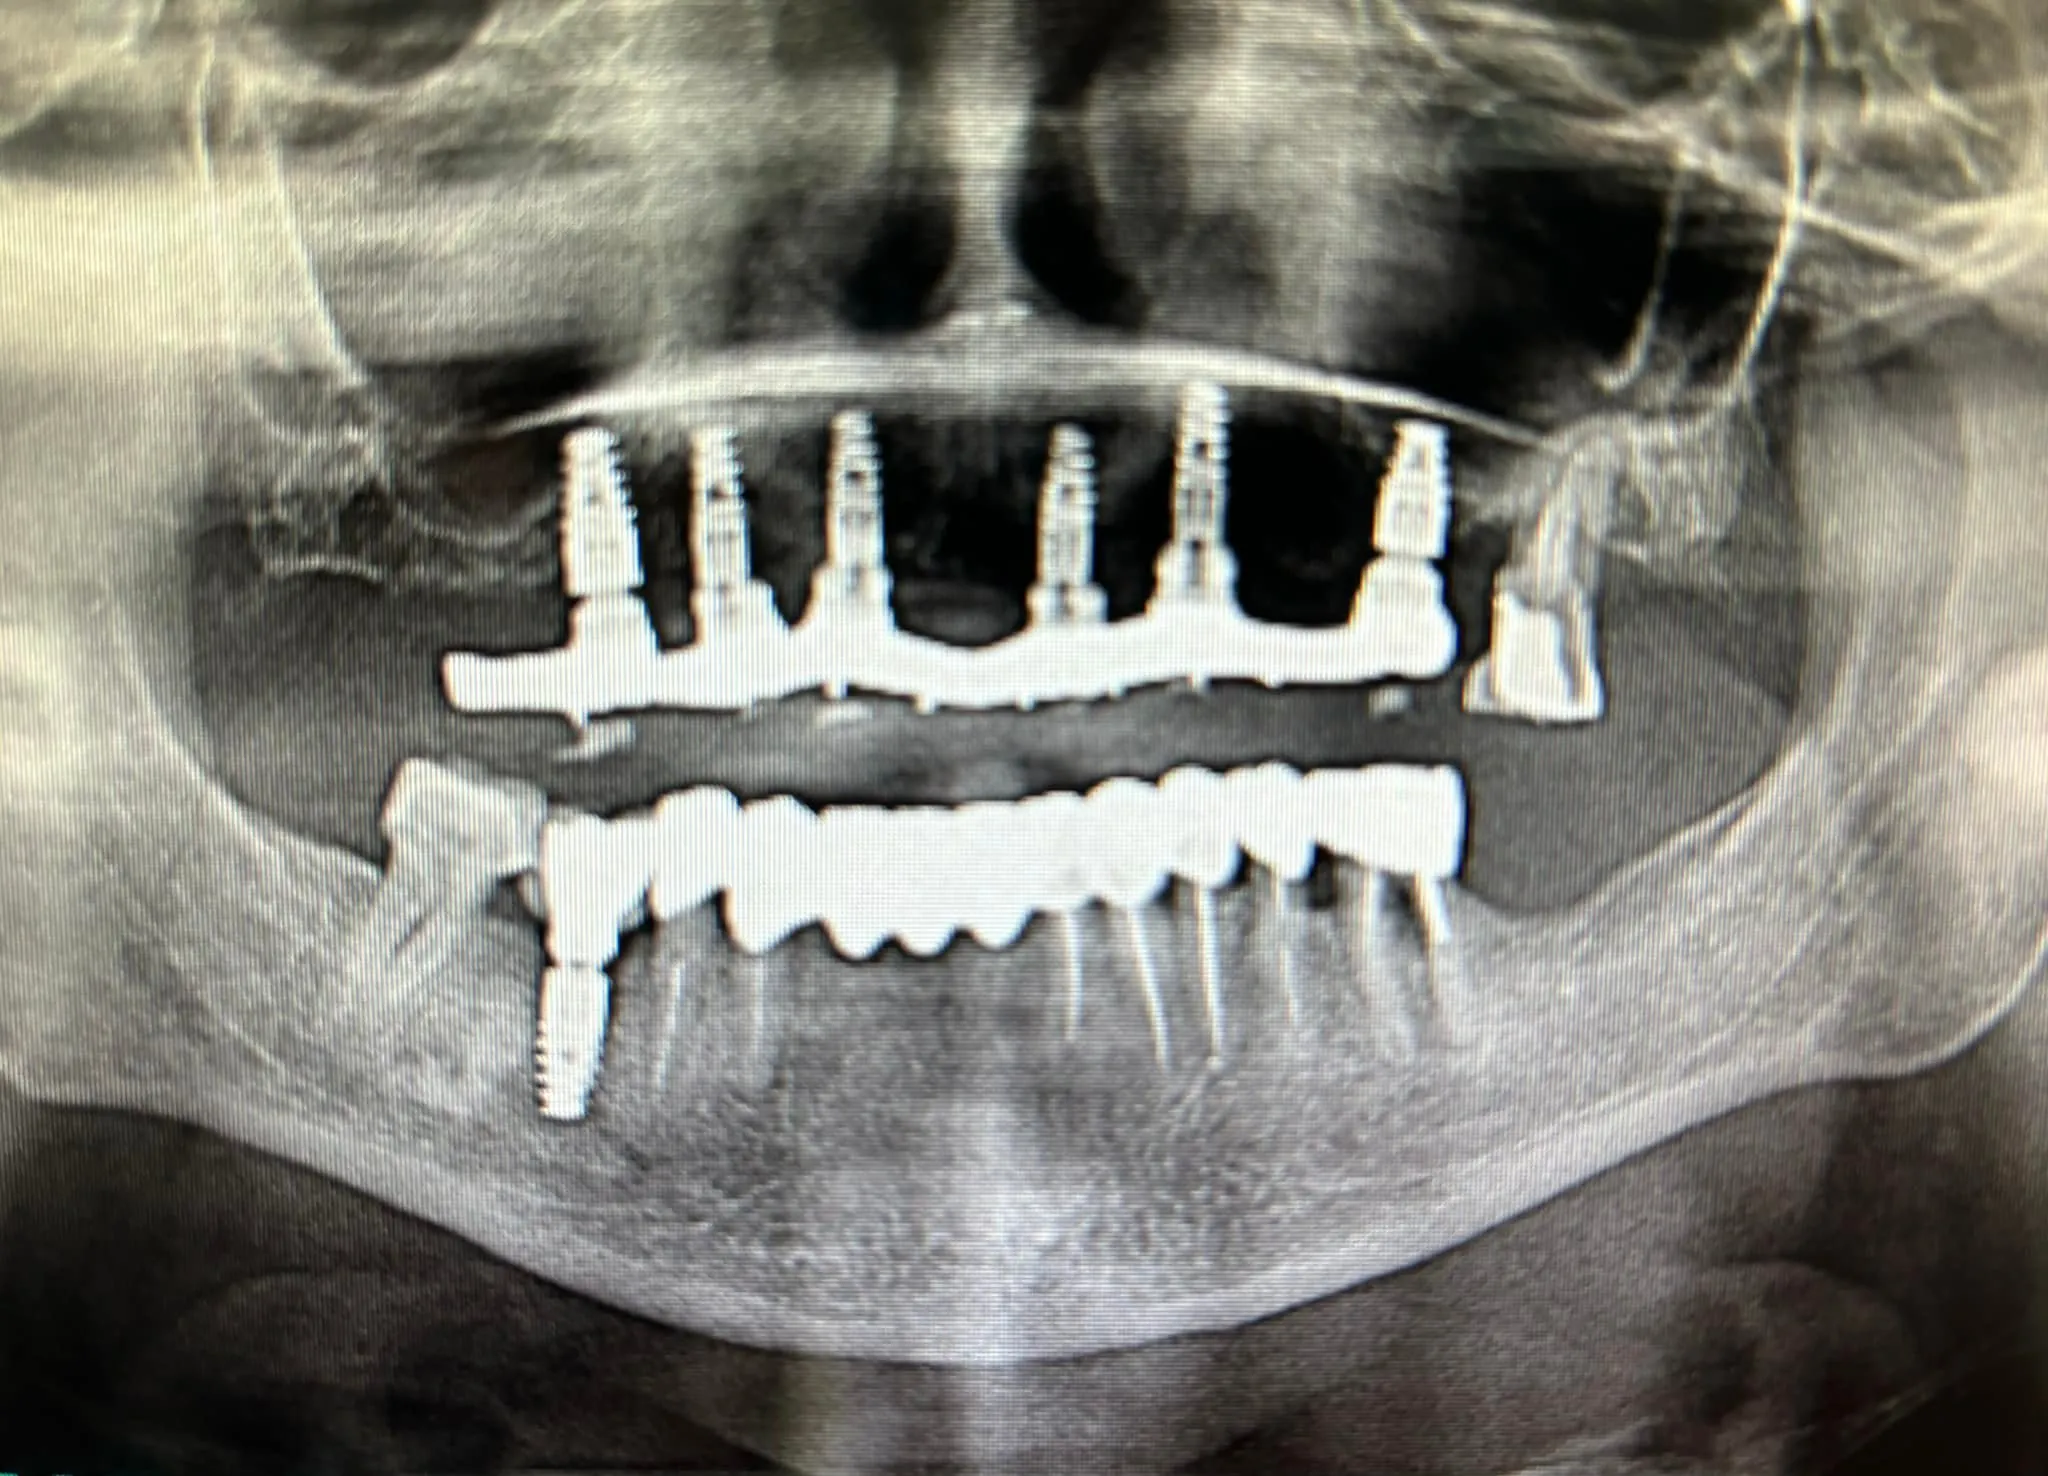

All-on-8 solution ultra-robuste

All-on-8

Pour les patients nécessitant une reconstruction complète, avec 8 implants pour une distribution optimale des charges et un résultat esthétique.

8 implants Esthétique Distribution optimale des forces